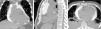

Images of the whole thorax were acquired before the procedure and were analyzed with dedicated software (Siemens Syngo Viewer®). Parameters used by protocol were: tube voltage 100 kV, tube current 110 mAs, reconstruction with 0.75 mm sections, overlap 0.5 mm. Typical window width/level used during the procedure was 700/80. The best entry point and needle orientation were determined (Figure 1). We used an 18 gauge needle from the PeriVac™ kit (Boston Scientific®). After superficial needle insertion, new images of the area of interest were acquired. Needle orientation was corrected as needed and the needle was advanced under aspiration. New images were acquired as needed. When the pericardial space was reached, a drain (8.3F pigtail catheter from the kit) was inserted through a guidewire (J-tipped 0.035″×80 cm) and final images were acquired. When in doubt (due to limited pericardial width at the puncture site) a small amount of contrast (by protocol 5 ml diluted in 10 ml of saline) was injected to confirm an intra-pericardial needle position before dilation and drain insertion (Figure 2).